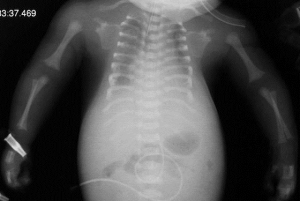

A avaliação radiográfica permite a confirmação do diagnóstico, com as seguintes características tipicamente encontradas: tórax em forma de sino; clavículas de guidão; costelas horizontais, bulbosas e muito mais encurtadas; ossos longos suavemente encurtados; configuração pélvica característica e cone de epífises nas mãos (em uma idade mais avançada).